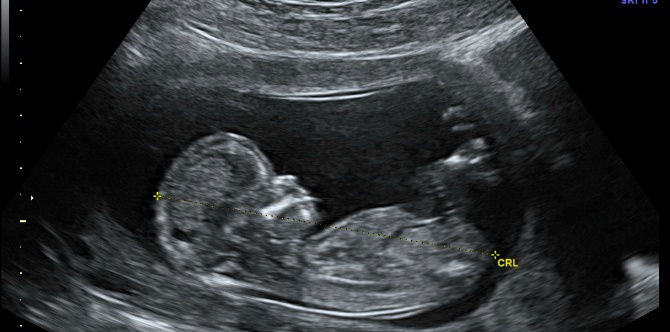

Image source: iStock